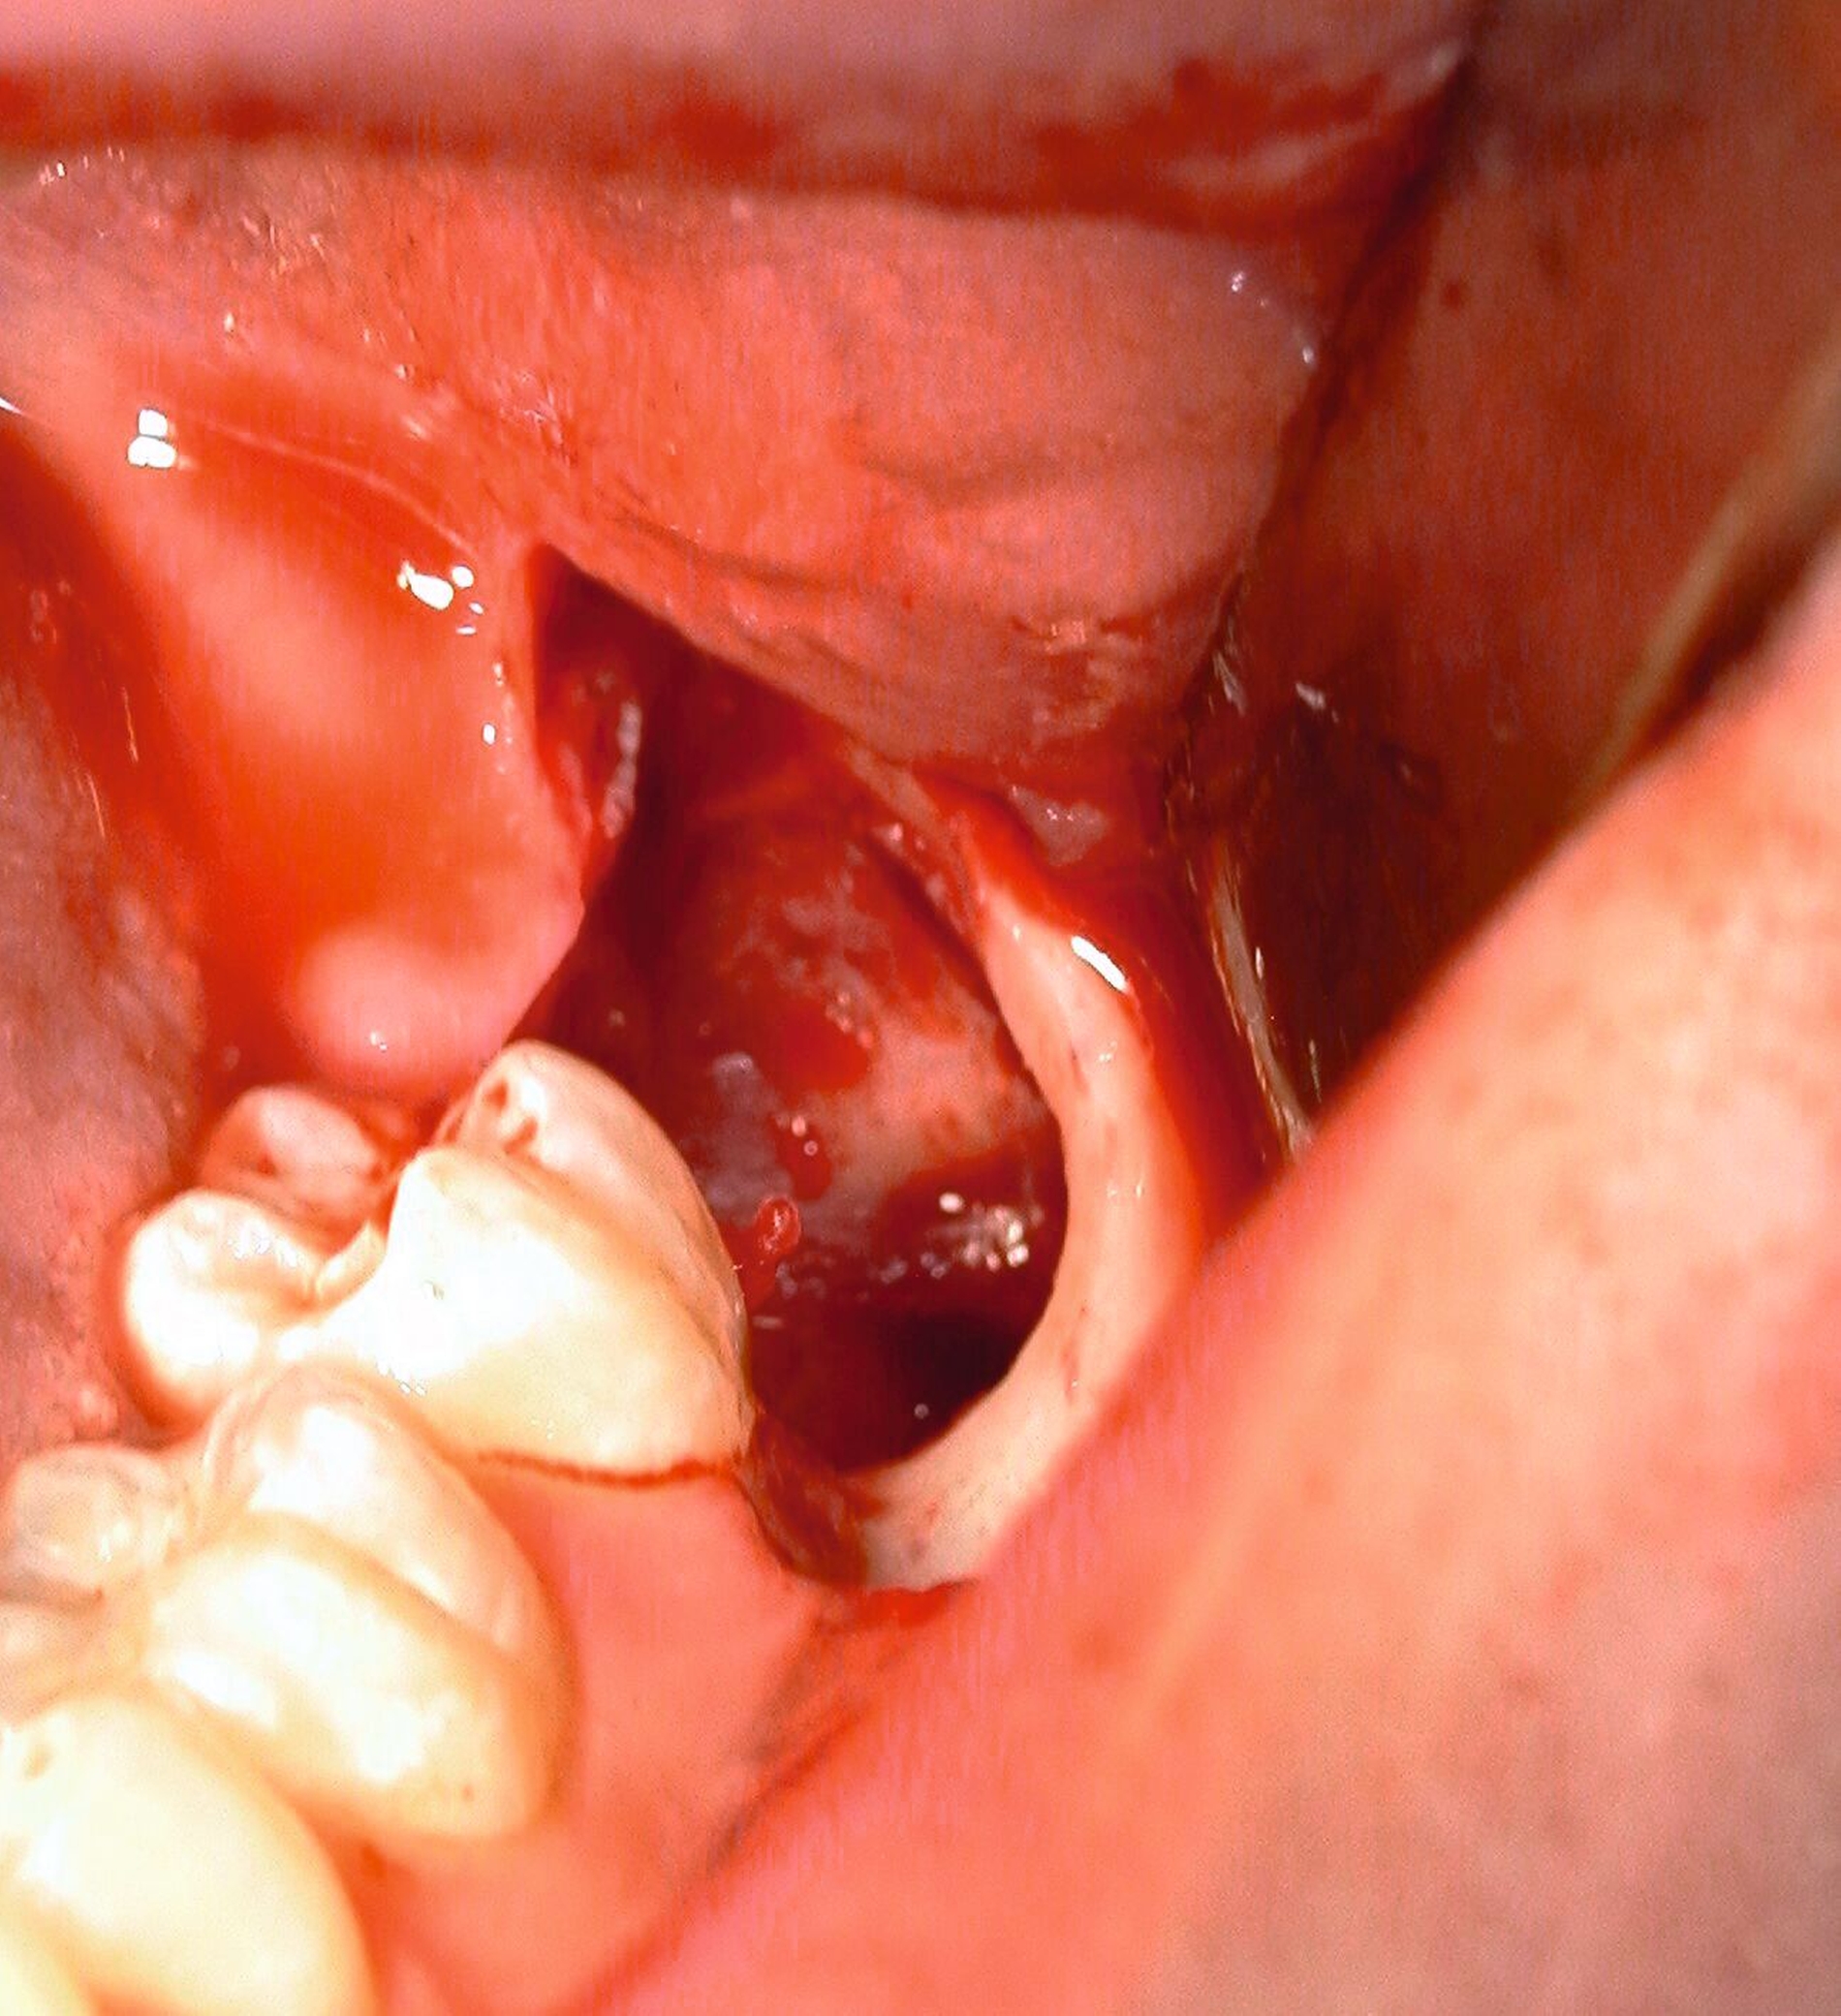

Die Vorgehensweise ähnelt der konventionellen Weisheitszahnentfernung im Unterkiefer. Zunächst wird ein Mukoperiostlappen gebildet und die Zahnkrone freigelegt. An der größten Zirkumferenz wird diese mittels Lindemann-Fräse unter ständiger Wasserkühlung und anschließend mithilfe eines Bein´schen Hebels abgetrennt. Dabei sollte der Wurzelblock nicht anluxiert werden, da er sonst aufgrund eines erhöhten Infektionsrisikos entfernt werden muss. Alle Schmelzanteile werden entfernt, der verbleibende Wurzelblock und die Knochenkanten geglättet (Abbildung 16). Auf eine weitere Behandlung der Wurzelpulpen kann verzichtet werden [Wolf & Renton, 2016].

Nach ausgiebiger Kürettage, der Entfernung von Granulationsgewebe und Spülung erfolgt der Wundverschluss wie bereits beschrieben. Zur Kontrolle kann eine postoperative zweidimensionale Bildgebung durchgeführt werden (Abbildung 17), auch um zu beurteilen, ob alle Schmelzanteile der Zahnkrone entfernt wurden.